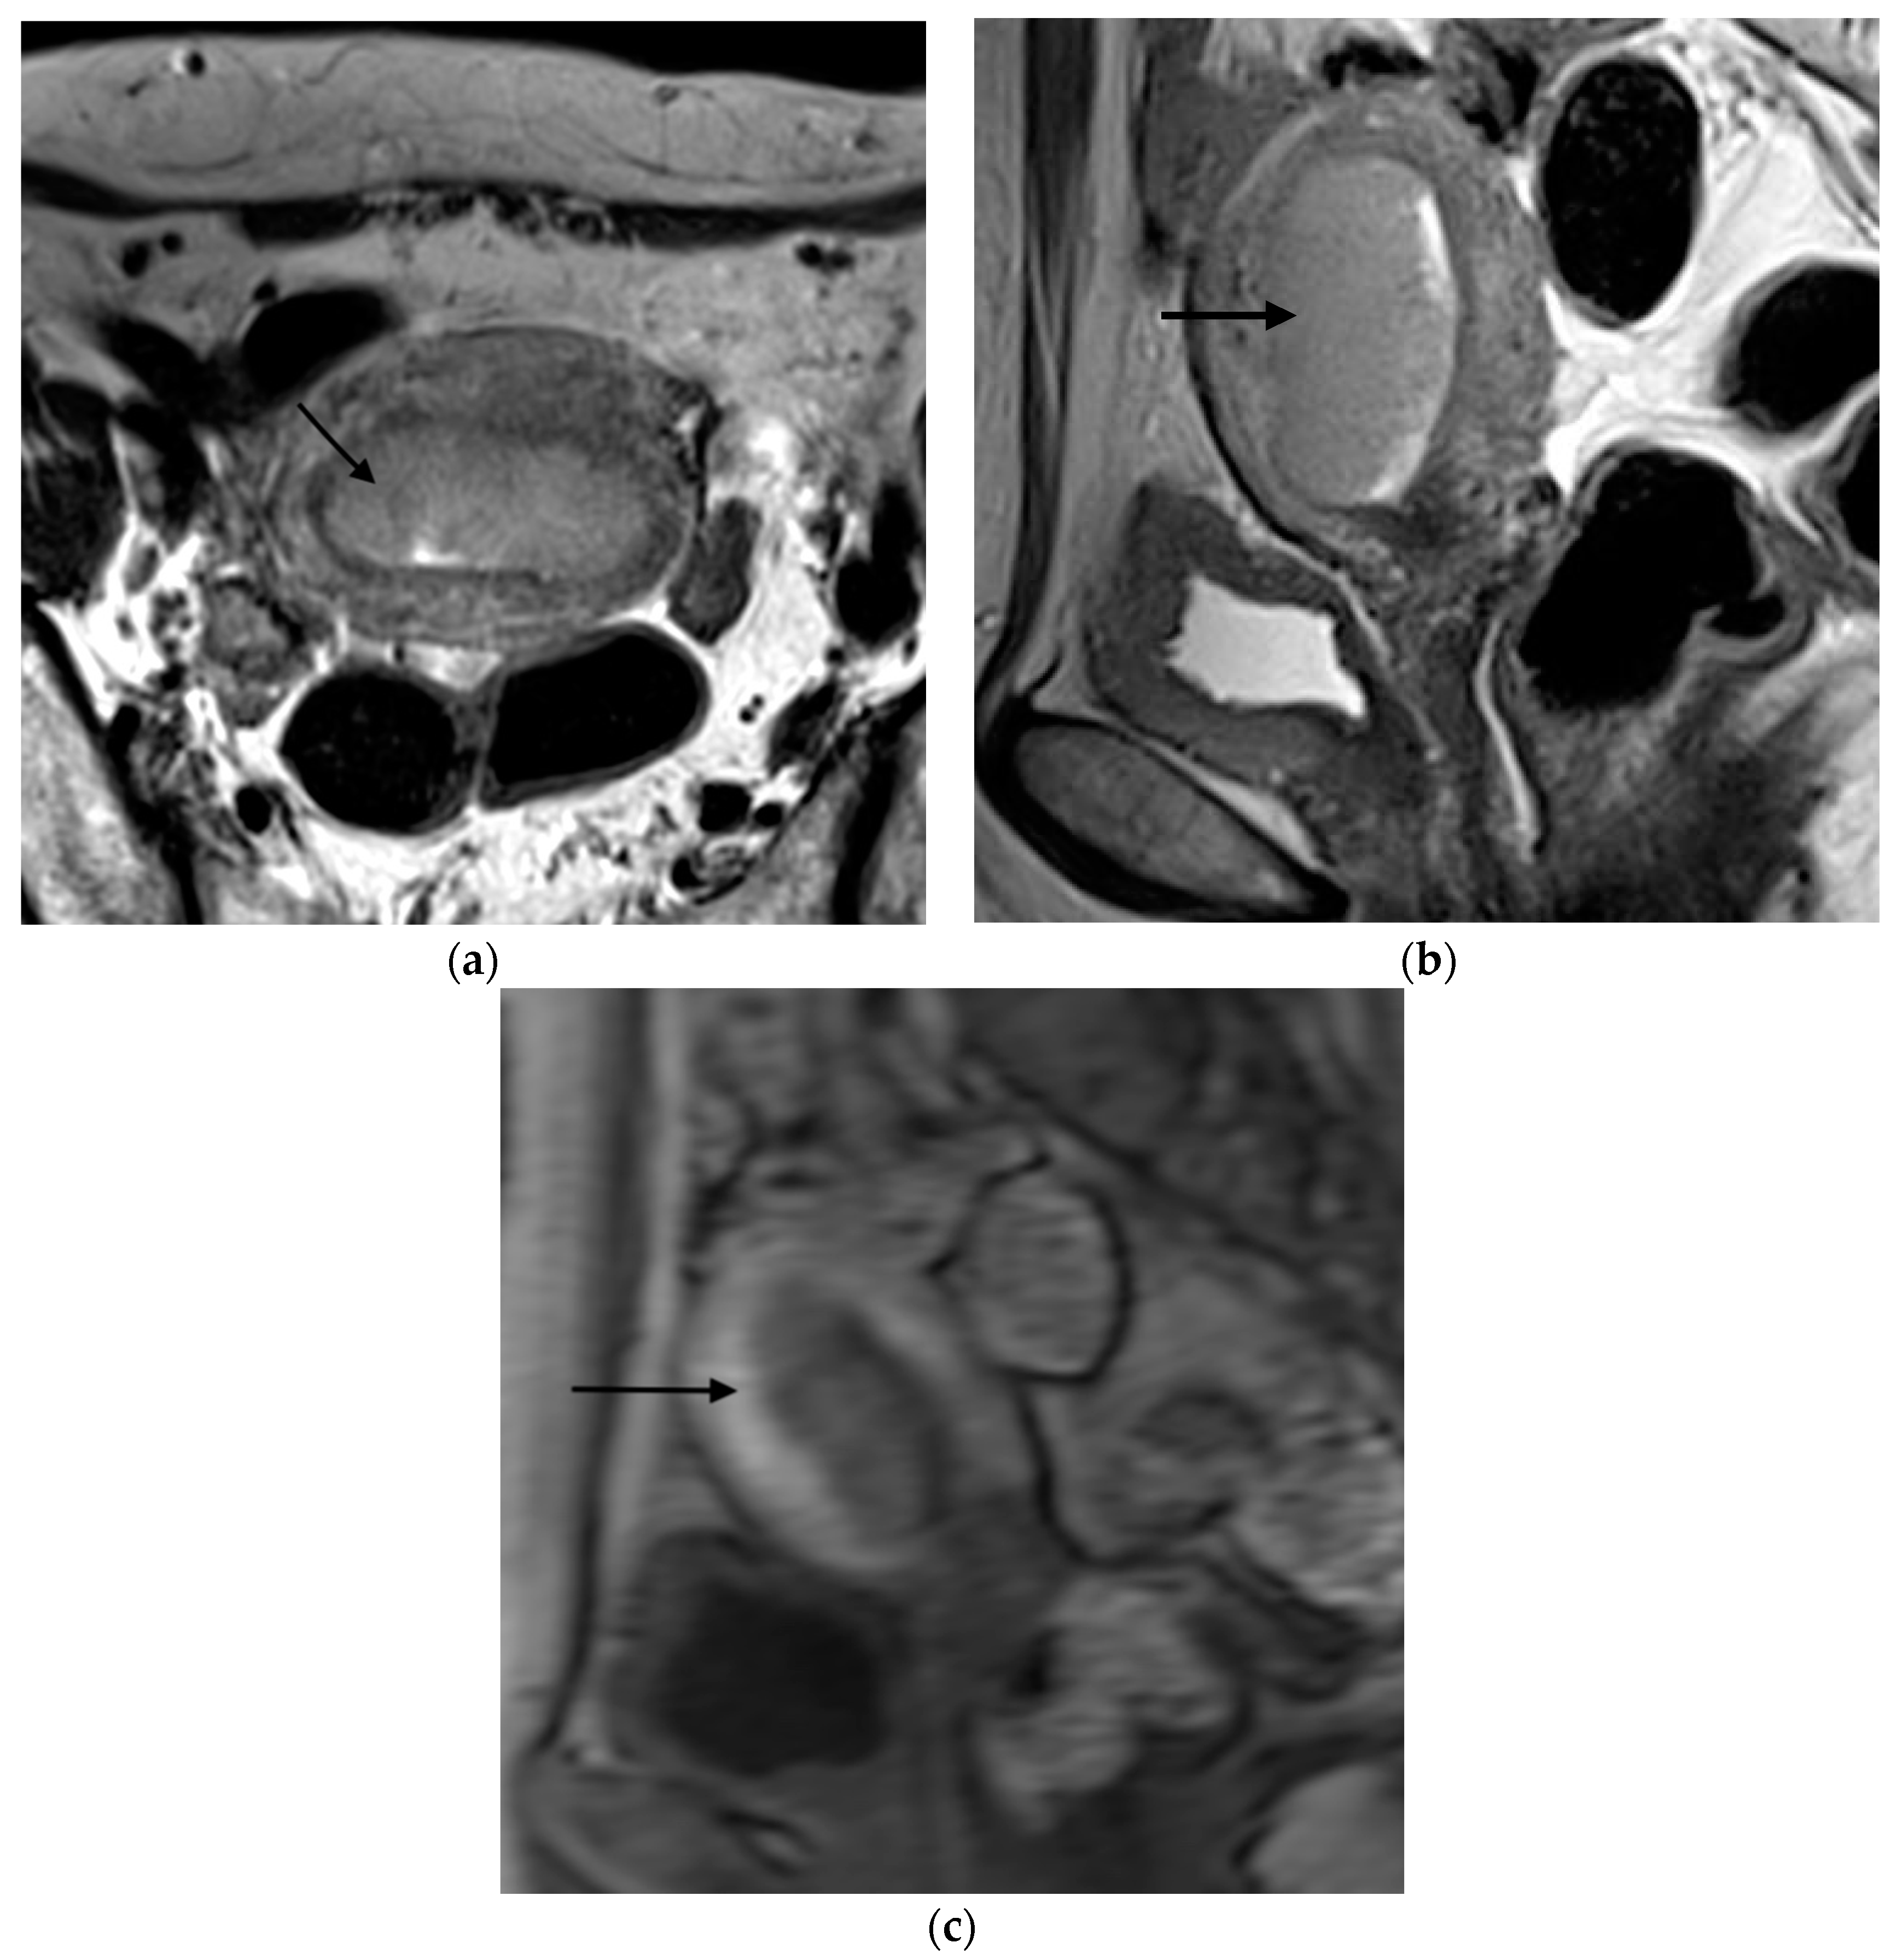

Figure 1, Figure 2, Figure 3 and Figure 4 depict the representative MRI images of tumors with < 50% myometrial invasion and ≥50% myometrial invasion, as well as the representative combined T2WI+DCE-MRI images for false-positive and false-negative cases, respectively. The diagnostic performance of MRI in predicting the depth of myometrial invasion is presented in Table 2 and Table 3. The depth of myometrial invasion (any depth) was correctly determined in 75% (n = 24) and 78% (n = 25) of cases on T2WI and DCE-MRI alone, respectively, whereas the percentage increased to 91% (n = 29) of cases when the T2W images were read together with those obtained by DCE-MRI.

Figure 4. Representative MRI images of endometrial carcinoma of a false-positive case in a 67-year-old postmenopausal woman. (a) Sagittal T2WI MRI image shows a slightly hyperintense lesion with disruption of the junctional zone (arrow). (b) DCE-MRI image shows a hypointense lesion with thinning of the myometrium and ≥50% myometrial invasion. Subendometrial enhancement was not visible. However, the histopathological result revealed <50% myometrial invasion.